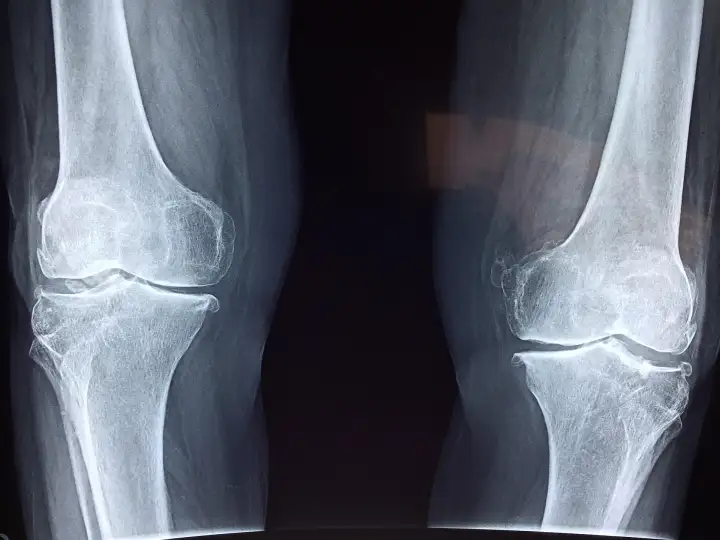

Замена коленного сустава может значительно улучшить качество жизни пациента.

Замена коленного сустава может значительно улучшить качество жизни пациента, если только не разовьётся инфекция. Хотя большинство операций по замене тазобедренных и коленных суставов обычно проходят хорошо, частота постоперационной инфекции может достигать 2%. Поэтому учёные из австралийского Университета Флиндерса создали соединение с жидким металлом, чтобы устранить этот вредный побочный эффект.